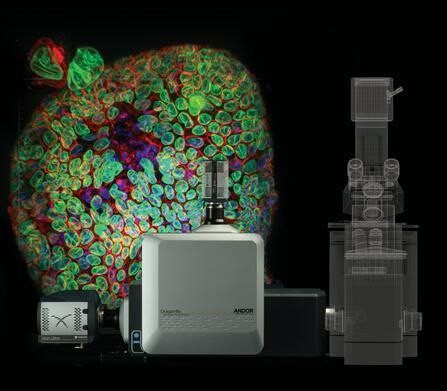

Dragonfly多点扫描共聚焦成像系统

项目类型

器械质押区

起投金额

18000USDT

每日释放:0.75

释放周期:70 天

已购: 2000

剩余: 0